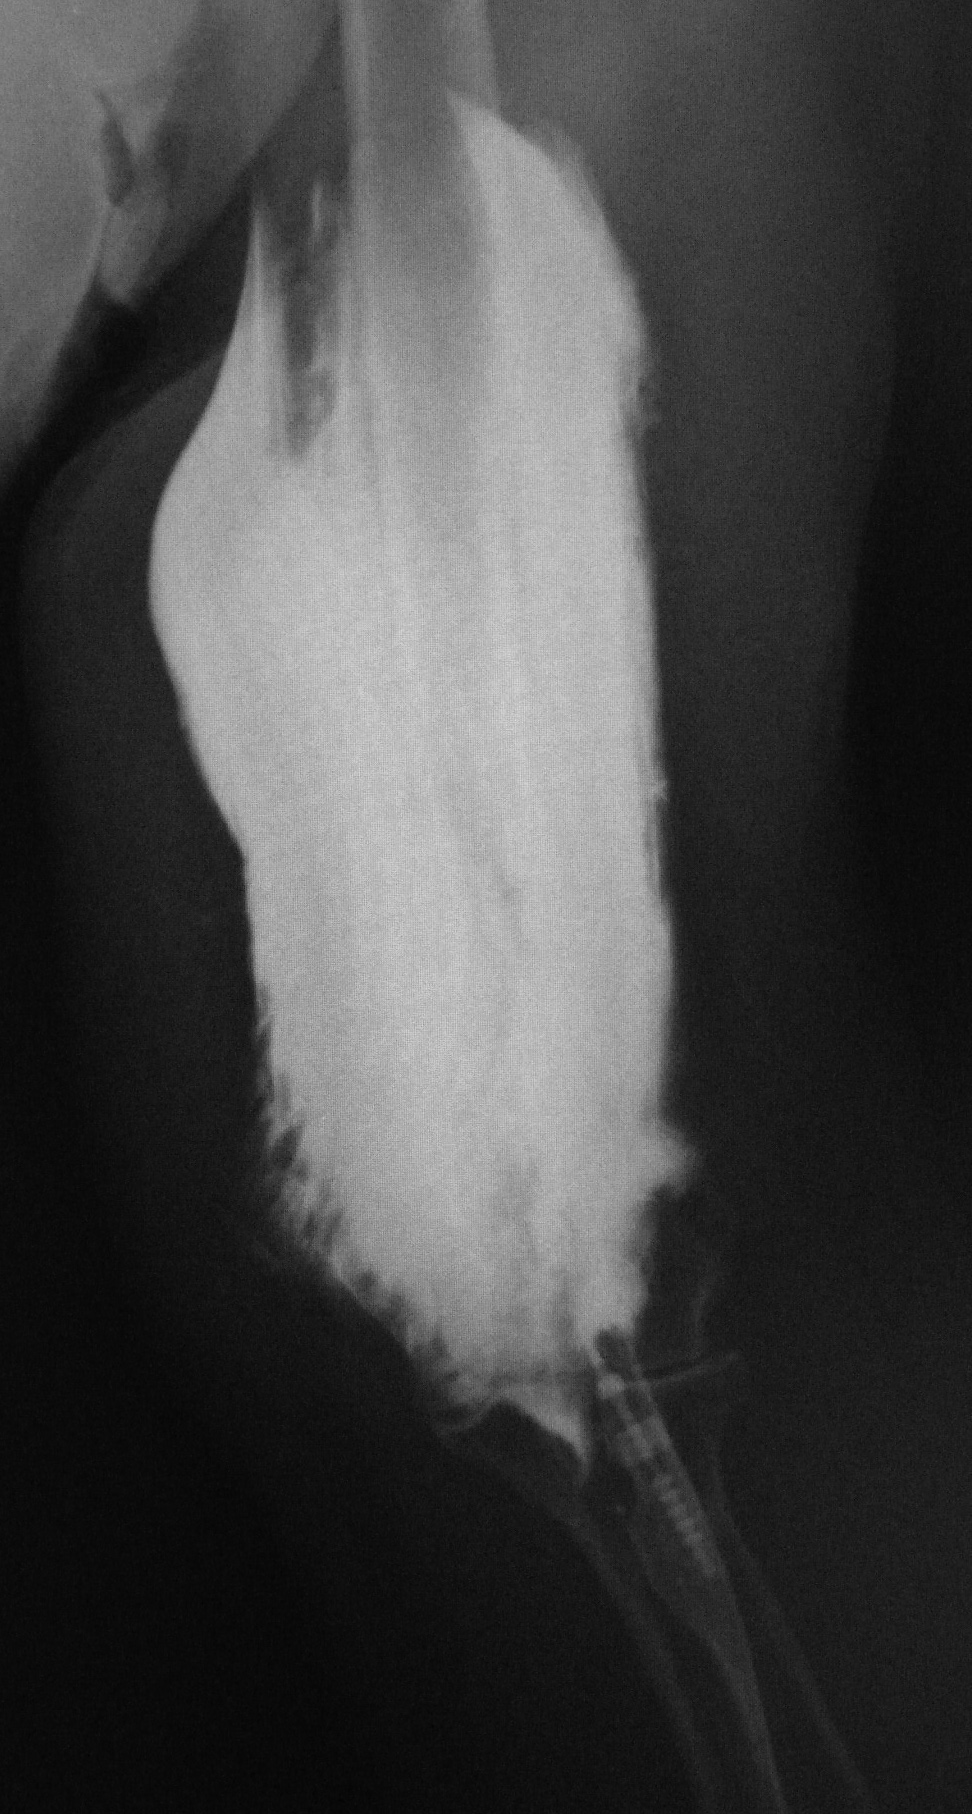

A county jail prisoner got into a dispute with another prisoner who forcibly poked a toothbrush into his chest wall (arrow). The bristles of the toothbrush are radio-opaque. |